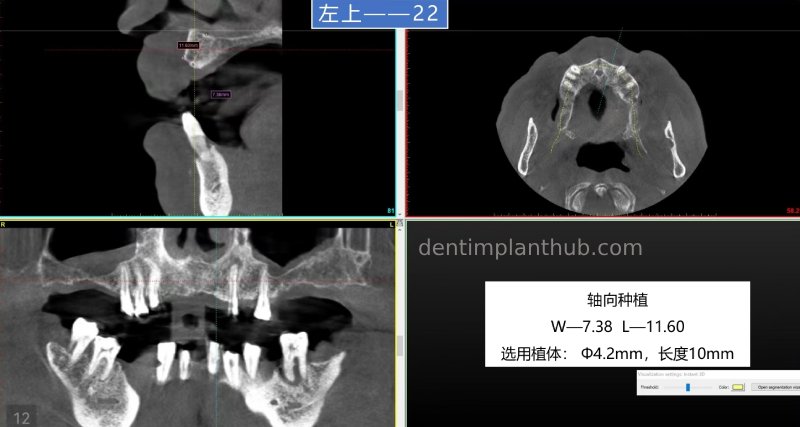

12, 22 normal implantation;

22, implant model 3810;